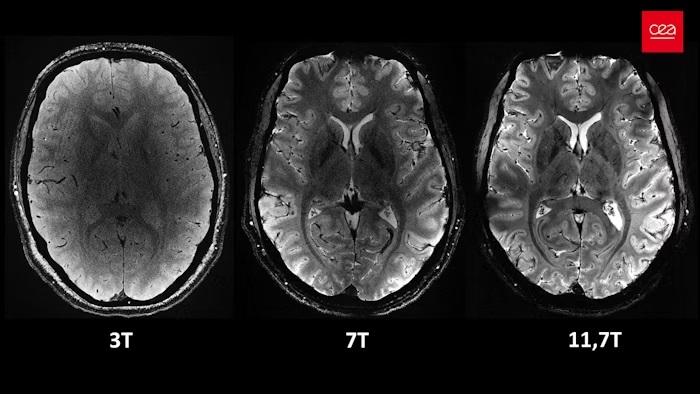

Scientists in France have achieved a major breakthrough in brain imaging, capturing the first ever MRI scans of the human brain in vivo at an incredible field strength of 11.7 tesla. This cutting-edge technology promises to revolutionize our understanding of the brain and unlock new possibilities for diagnosing and treating neurological disorders.

The project, known as Iseult, is the culmination of over two decades of research by a team at NeuroSpin, a leading brain imaging facility near Paris. The new MRI scanner boasts a magnetic field strength ten times stronger than those used in conventional hospital machines. This immense power translates into stunningly detailed images of the brain, revealing structures as small as a few thousand neurons.

"The first images surpassed our expectations," said Professor Denis Le Bihan, the project's leader. "We were able to capture mind-blowing brain images in just four minutes, with incredible detail and clarity." These images, he explains, would require hours to obtain with current MRI technology.